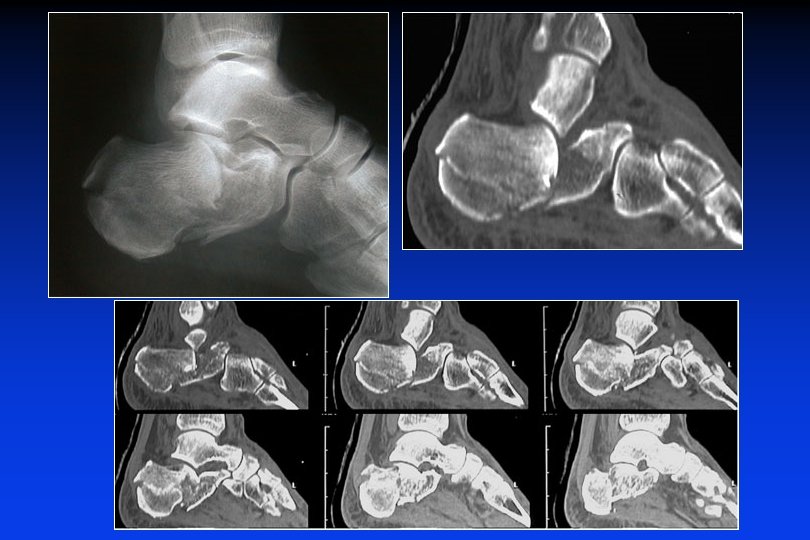

RADIOGRAFIE SEMPLICI TAC pre-operatoria III IV V Foto JL Besse

TAC Foto JL Besse

TAC pre-operatoria II B Incongruenza sotto-talamica post. : 90 % Conflitto malleolare esterno : 80 % Lesioni della calcaneo-cuboidea : 40 %

TAC pre-operatoria